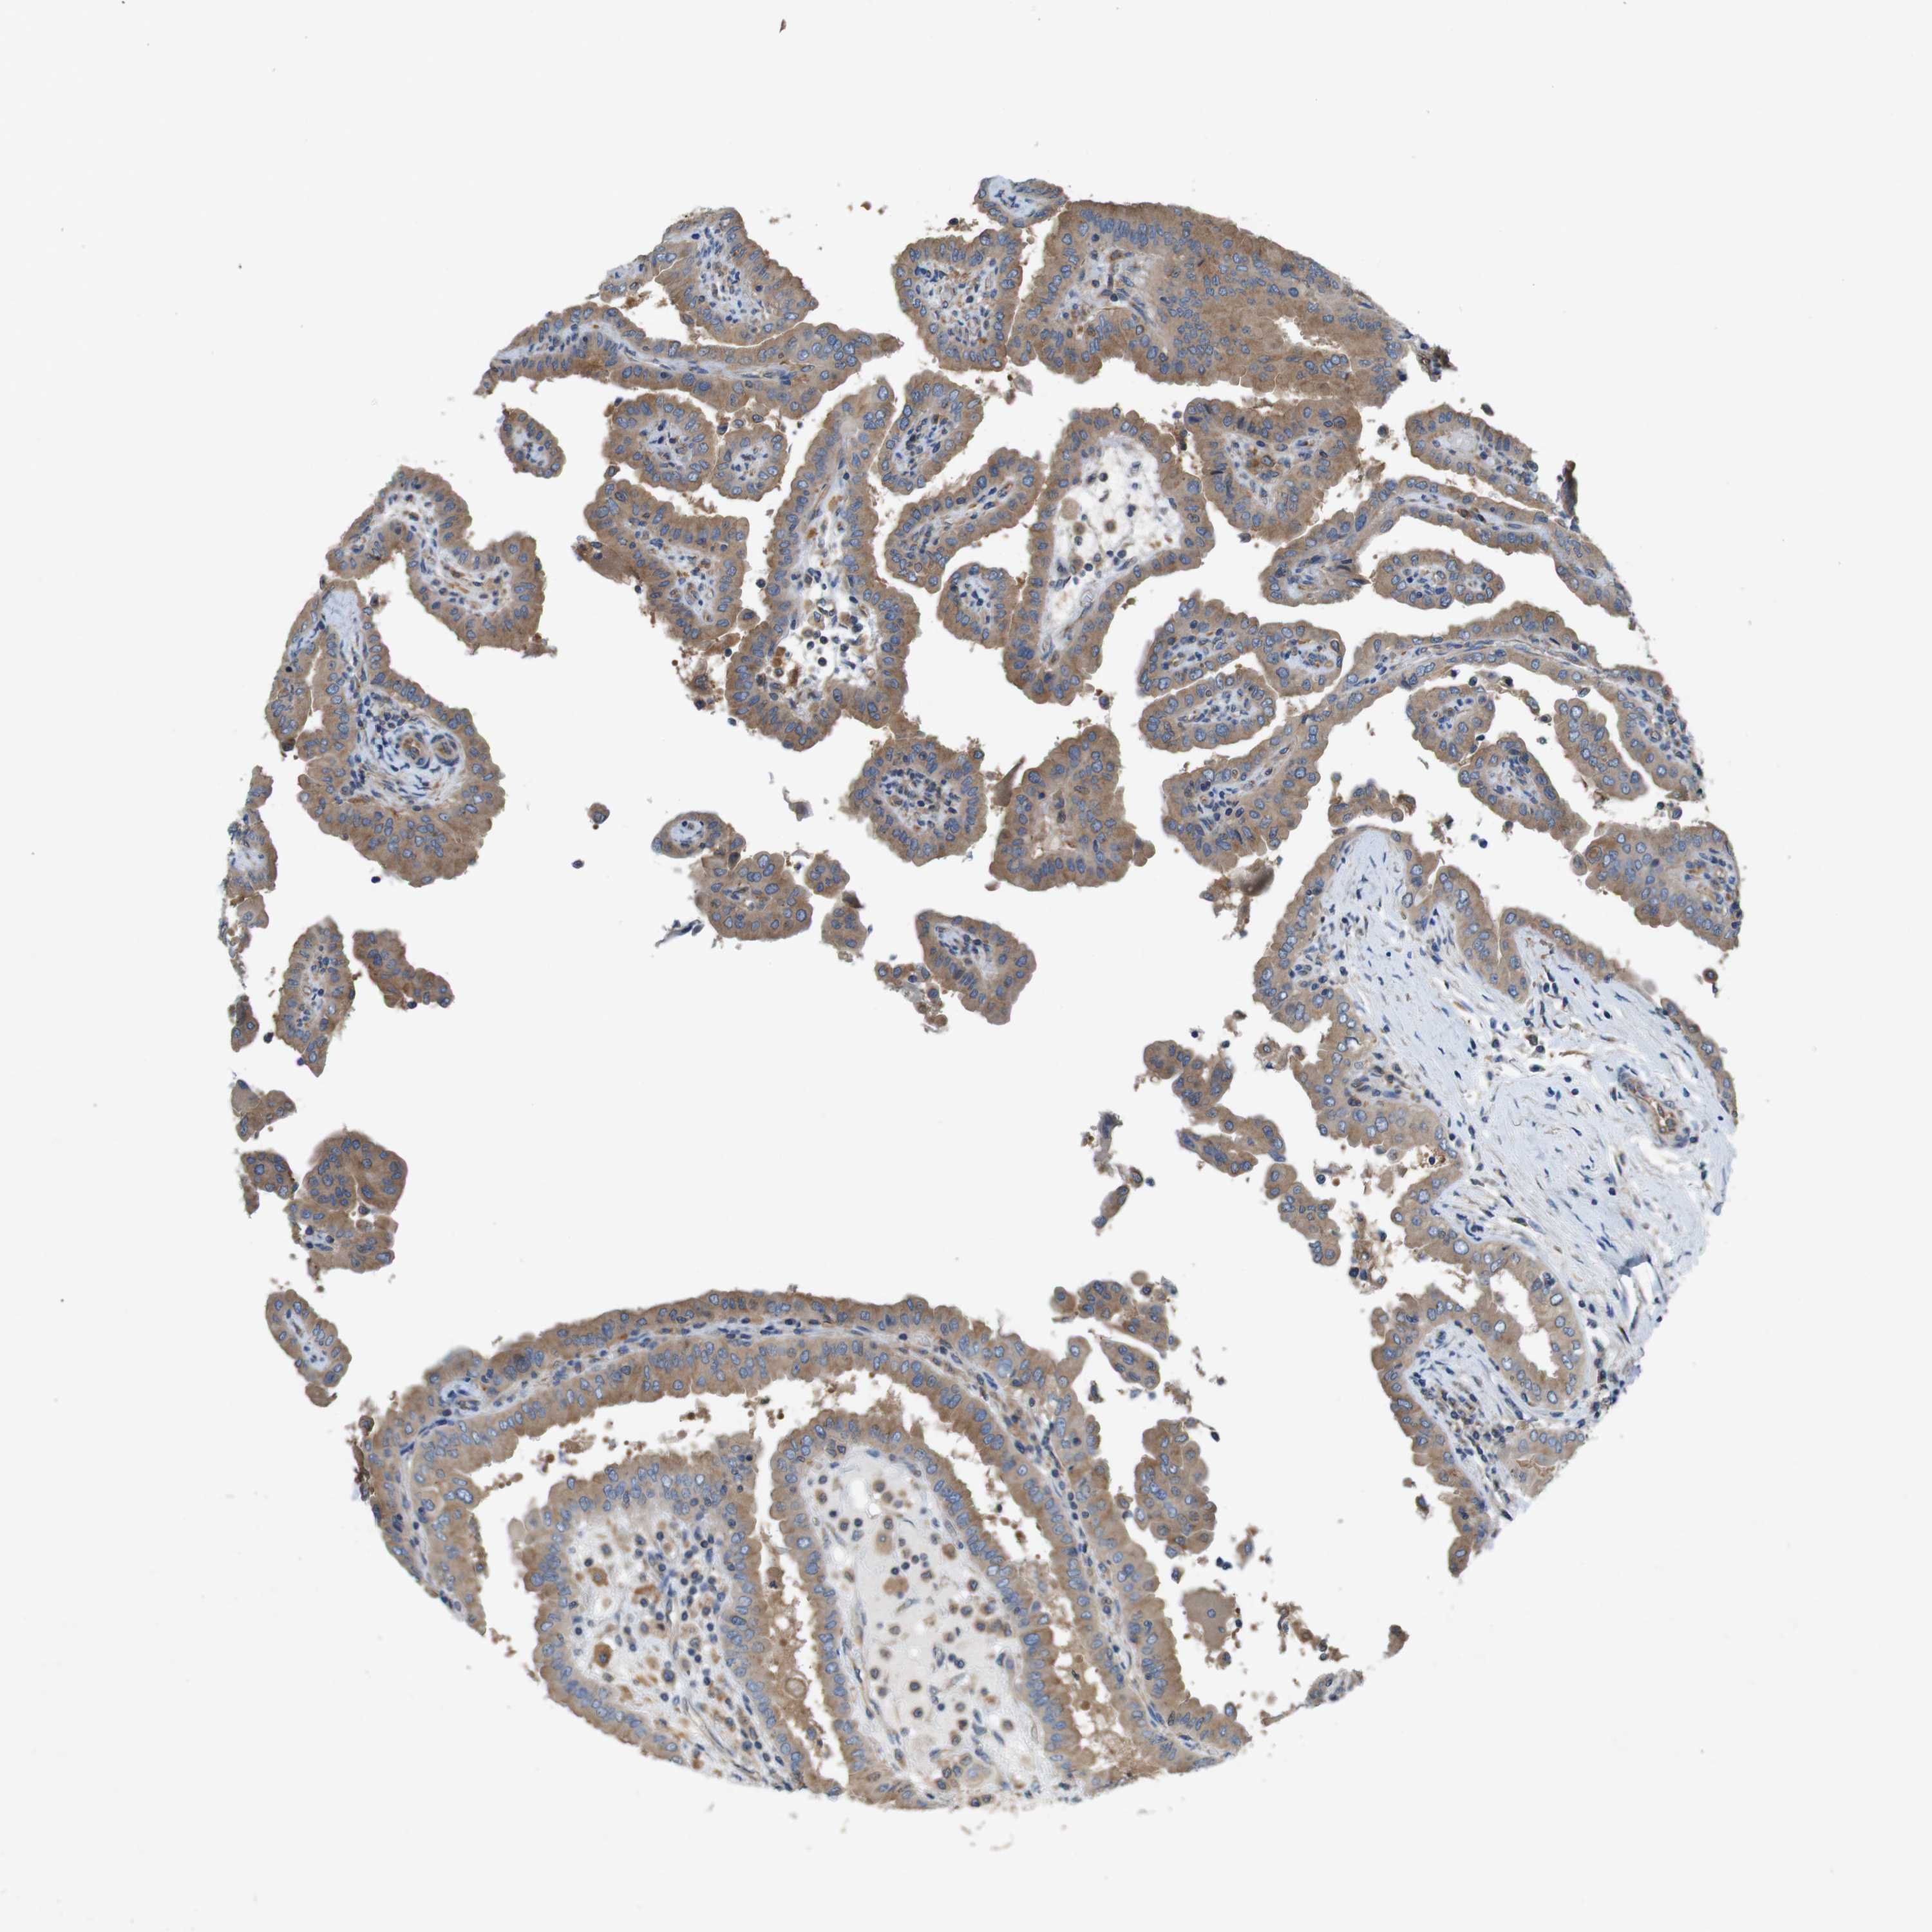

THYROID CANCER - Protein expressioni

A mouse-over function shows sample information and annotation data. Click on an image to view it in a full screen mode. Samples can be filtered based on level of antibody staining by selecting one or several of the following categories: high, medium, low and not detected. The assay and annotation is described here.

Note that samples used for immunohistochemistry by the Human Protein Atlas do not correspond to samples in the TCGA dataset.

Antibody stainingi

Antibody staining in the annotated cell types in the current human tissue is reported as not detected, low, medium, or high, based on conventional immunohistochemistry profiling in selected tissues. This score is based on the combination of the staining intensity and fraction of stained cells.

Each image is clickable and will lead to virtual microscopy that enables deeper exploration of all samples and also displays staining intensity scores, fraction scores and subcellular localization as well as patient and tissue information for each sample.

Antibody HPA069977

Staining

High

Medium

Low

Not detected

Intensity

Strong

Moderate

Weak

Negative

Quantity

>75%

75%-25%

<25%

None

Location

Nuclear

Cytoplasmic/membranous

Cytoplasmic/membranous,nuclear

Papillary adenocarcinoma, NOS

Follicular adenoma carcinoma, NOS